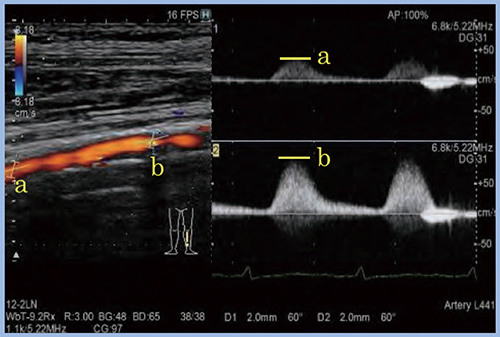

3.Dual Gate Doppler

下肢動脈検査における収縮期最大血流速度比(PSVR)は,パルスドプラ(PW)法を用いて,まず狭小化部位の中枢側で血流速度を測定し,次に極小化部位の収縮期最大血流速度(PSV)を測定して,手動計算にて算出する。一方,“Dual Gate Doppler”では,同一心拍にてサンプルゲートを2か所設定し,同一画面上で同時に血流速度波形を評価できるため,PSVR測定が容易となり(図6),精度向上にも貢献する。

図6 Dual Gate Dopplerを用いたPSVRの測定